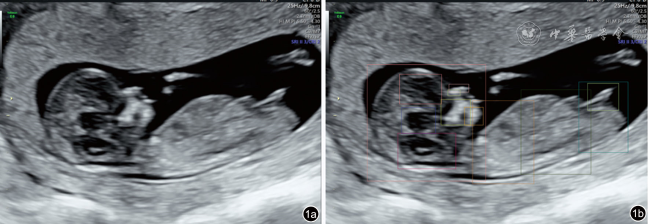

图1 产前超声人工智能智慧云平台对胎儿头臀长切面质量控制超声图像。质量控制结果包括检测结构显示情况(鼻骨、鼻尖和鼻前皮肤、上颌骨、下颌骨、间脑、菱脑、生殖器、侧脑室、头、胸、腹、臀)和总体评价,总体评价包括切面名称、切面质量(标准)、切面评分(94分)、结构置信系数评价(鼻骨:0.53,鼻尖和鼻前皮肤:0.68,上颌骨:0.86,下颌骨:0.46,间脑:0.89,菱脑:0.83,生殖器:0.80,侧脑室:0.69,头:0.89,胸:0.80,腹:0.81,臀:0.78)及不足原因。图a为原图,图b为质量控制标注图 |